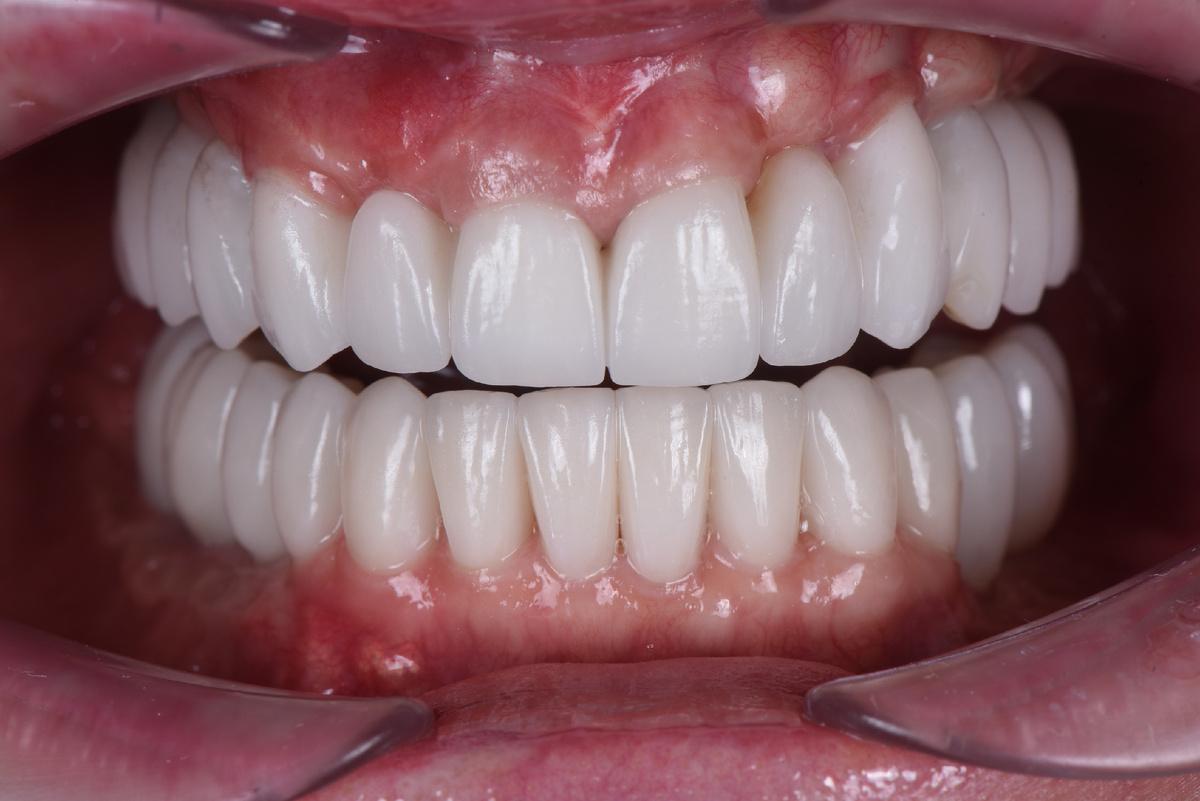

Протезирование

Оставим за скобками мероприятия по изготовлению временных конструкций, служивших не более, чем небольшим утешением нашей героине. Основная работа началась после имплантация зубов верхней челюсти, по традиции, с моделирования будущей улыбки на экране монитора (DSD)

Первая примерка :

Верхняя челюсть: 2 мостовидных протеза в жевательных отделах с опорой на 3 имплантата и мост на 6 единиц с опорой на 4 собственных зуба

Следующий шаг — коронки на нижние зубы:

Завершающий этап — после протезирования на имплантатах на нижней челюсти слева, в той области, где костная ткань восстанавливалась дольше всего